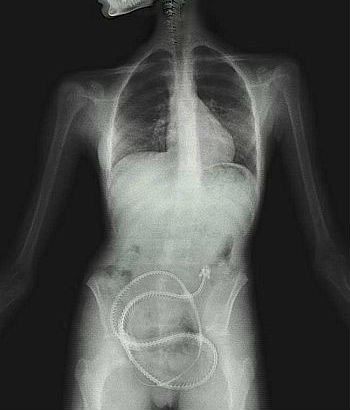

La historia se dio a conocer después de que una mujer de Iowa acudiera al médico a confesarle que compró una lombriz solitaria por Internet y la tragó en su afán de perder peso. Como era obvio, el médico quedó impactado, así que se comunicó inmediatamente con el Departamento de Salud Pública de Iowa para obtener orientación.

Según Huffpost Voces, la instrucción fue matar y extraer el parásito de inmediato con la ayuda de un medicamento especial. El caso se extendió vía Internet a todos los empleados de salud pública por la directora del Departamento de Salud, la Dra. Patricia Quinlisk.